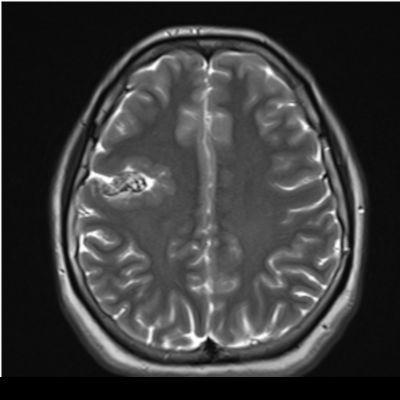

29 yaş, K

Baş ağrısı

Arteriyovenöz Malformasyon

AVM